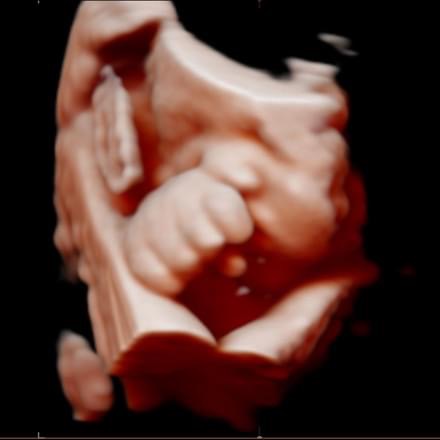

All photos are from our equipment and are of our actual clients.